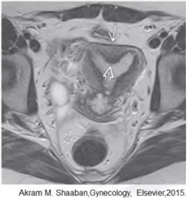

纵隔子宫

最常见,双侧副中肾管融合后,中隔吸收受阻,而形成不同程度的纵隔

分型

完全性:纵隔由宫底达到宫颈内口或外口

部分性:纵隔由宫底未达宫颈内口

需与双角子宫鉴别

纵隔子宫宫底外形正常或轻度凹陷小于1cm,双角子宫则宫底外形凹陷大于1cm

纵隔子宫两角间距小于4cm,双角子宫则大于4cm

纵隔子宫两角夹角小于75°,双角子宫则大于105°

子宫外形正常,宫腔内可见纵隔影将宫腔分离,呈纤维性或肌性信号